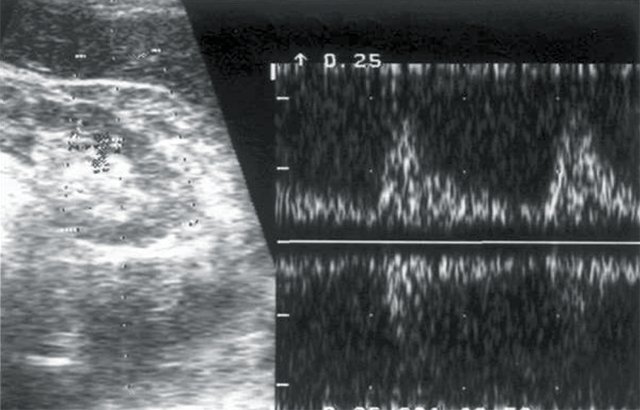

У 12 больных при допплерографии почечных артерий был выявлен высокорезистивный кровоток в основном стволе, сегментарных и дуговых артериях паренхимы, показатели АД были стабильно повышены, диастолическое АД равнялось в среднем 105±0,05 мм рт.ст. (рис. 5) У 8 пациентов с артериальной гипертензией эхогенность почечной паренхимы была повышена, нарушена кортико-медуллярная дифференцировка паренхимы, размеры почек находились в пределах нормы. В анализах мочи наблюдались высокий удельный вес мочи, лейкоцитурия, альбуминурия. Во всех случаях больным с диффузным нефротическим сонографическим синдромом проводилась допплерография почечных артерий для исключения экстравазальной компрессии и выявления артериовенозного шунтирования в паренхиме почек (рис. 6, 7).

а) Эхограмма правой почки.

б) Кровоток в основном стволе правой почечной артерии: систолическая скорость (Vс) - 45 см/с, диастолическая скорость (Vд) - 15 см/с, систолодиастолическое отношение (СДО) - 3,0, индекс резистентности (RI) - 0,67.

в) Кровоток в правой сегментарной артерии: Vс - 35 см/с, Vд - 8 см/с, СДО - 4,5, RI - 0,77.

г) Кровоток в дольковых артериях паренхимы правой почки: Vс - 18 см/с, Vд - 4,4 см/с, СДО - 4, RI - 0,75.